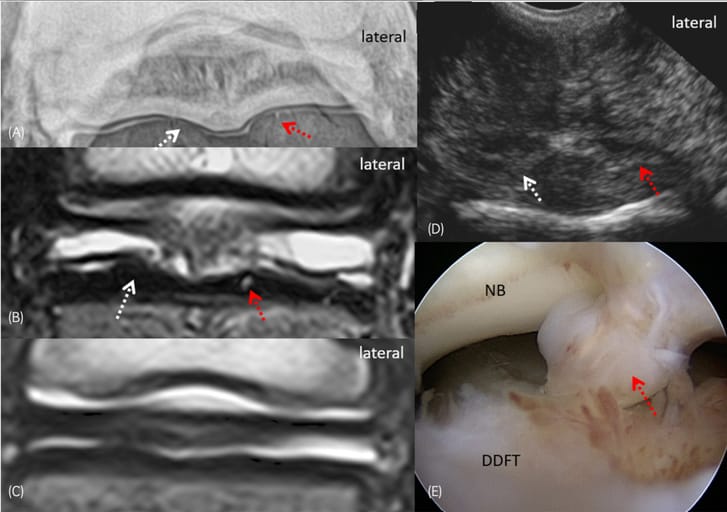

(A) Palmaroproximal–palmarodistal oblique bursography shows mild linear pooling of the contrast agent in the lateral lobe of DDFT lobe (red arrow) and focal interruption of the contrast column at the medial aspect (white arrows) of the navicular bone (NB). (B, C) T2 high resolution transverse image at the level of the proximal navicular bursa recess and the navicular bone respectively. The images show moderate distention of the proximal recess of the navicular bursa associated with thickening of the synovial membrane. There is also border effacement between the navicular bursa and the medial deep digital flexor tendon lobe (DDFT). The latter has mild dorsal fibrillation and frying (white arrow). The lateral DDFT lobe has focal hyperintense lesion in the dorsal aspect (red arrow). (D) Ultrasonography of the DDFT at the level of distal middle phalanx. The medial DDFT lobe has a smaller cross-sectional area compared to the lateral lobe and is associated with mild thickening of the dorsal aspect (red arrow). The lateral lobe has focal hyperechogenic area at the dorsal aspect (white arrow). (E) Bursoscopy showed adhesion formation with origin the DDFT (red arrow).